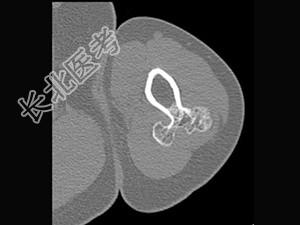

单项选择题男,28岁, 左手臂上部可扪及一硬结,有轻压痛, 结合图像,最可能的诊断是 ( )

A、骨软骨瘤

B、骨旁骨瘤

C、表面骨肉瘤

D、皮质旁软骨瘤

E、皮质旁软骨肉瘤